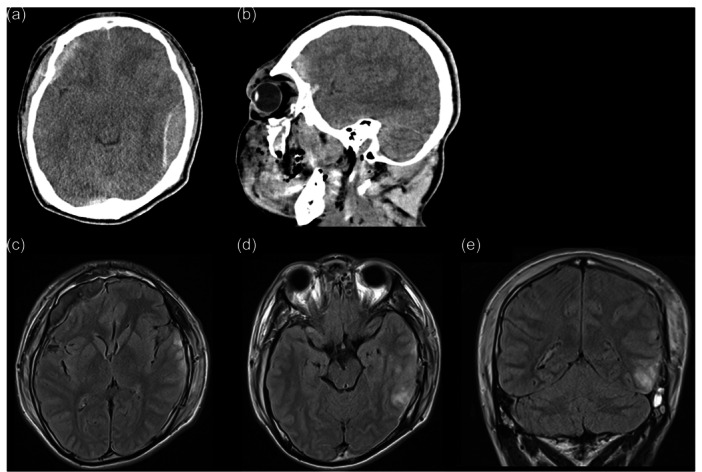

Case presentation: We report the case of a 17-year-old Japanese male who developed OCD after traffic trauma. The patient developed a fear of contamination and checking compulsion after injuring his right OFC and left temporal lobe when he ran into a running truck during a suicide attempt. We believe that the patient's fear of contamination can be diagnosed as true post-TBI OCD. However, his memory impairment was significant, and we considered his checking compulsion to be strongly influenced by cognitive dysfunction due to TBI. We attempted behavioral therapy for OCD; however, sufficient results were not achieved because of the interference from the sequelae of TBI.